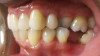

Fig 2. Candidates for hybrid teledentistry include patients with minor (Fig 2), moderate (Fig 3), and advanced crowding (Fig 4).

FIgure 2

Fig 3. Candidates for hybrid teledentistry include patients with minor (Fig 2), moderate (Fig 3), and advanced crowding (Fig 4).

Figure 3

Fig 4. Candidates for hybrid teledentistry include patients with minor (Fig 2), moderate (Fig 3), and advanced crowding (Fig 4).

Figure 4

The author's practice established a partnership with one of these disruptive clear aligner companies that offer this hybrid approach as a means of attracting consumers who were largely educated about the model and were seeking optimal results. The practice provides the initial case assessment and takes records to help the partner determine if the patient is a candidate for clear aligner treatment (Figure 2 through Figure 4), then it is compensated for these services. From this point on, the hybrid model involves teledentistry backed by state licensed dentists and orthodontists with minimal disruption to the practice. This, in itself, is a revenue builder, as it enables minimum aligner treatment cost to be paid with no additional fees or membership dues.